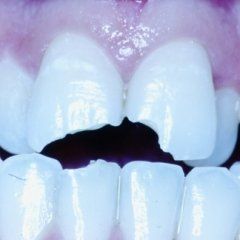

P3: Il trattamento endodontico si rende necessario quando la polpa del dente, comunemente chiamata dai Pazienti “nervo” è stata irrimediabilmente danneggiata da carie penetranti, fratture dentali, traumi o da cause imputabili a pratiche odontoiatriche scorrette. A volte la devitalizzazione del dente si rende necessaria, in corso di riabilitazioni protesiche complesse, per prevenire possibili problemi di ipersensibilità o per poter coinvolgere nel progetto terapeutico di recupero denti già di per se compromessi dal punto di vista parodontale. Presupposto per ottenere il successo in tale terapia è l’applicazione di un serio protocollo operativo che prevede tra l’altro l’uso di un telo di lattice, chiamato comunemente “diga”, che consenta la detersione e la pulizia dei canali del dente in un ambiente sterile e il controllo delle diverse fasi del trattamento attraverso delle radiografie endorali.